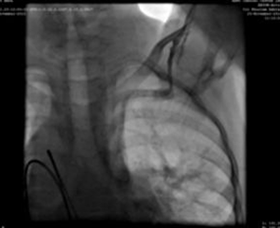

We used a 9F delivery sheath, which was advanced over and placed in the descending aorta over the super-stiff guidewire. A MemoriaTM cone shape PDA occluder 14/12 mm, was attached to the delivery cable and progressed across the delivery sheath. The placement of the occlude was proper with no residual flow.

Successo chirurgico, nessuna complicazione intraoperatoria grave, l'ecocardiografia 24 ore dopo l'occlusione mostra un buon posizionamento, nessuno shunt residuo sul difetto.